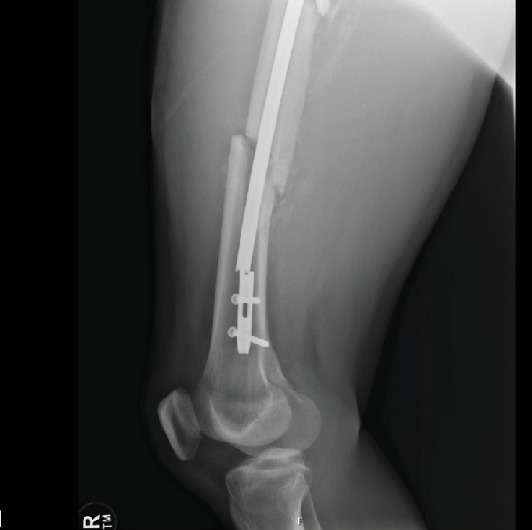

This case report from a Level 1 trauma center describes a novel surgical technique to remove a cannulated intramedullary nail, broken at the distal aspect, from the femur. We present a 40-year-old male who sustained a hardware failure, breaking his medullary nail at the distal aspect 7 weeks postoperatively while performing water aerobics. The broken implant was successfully extracted without complication, and a subsequent nail was exchanged. A benefit of this technique is avoiding a femoral osteotomy, which may prove useful for the unique and difficult case of distally broken nails.